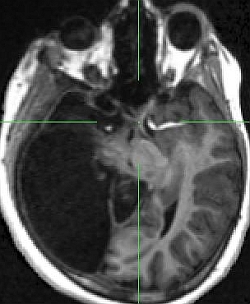

University of Glasgow researchers used Functional Magnetic Resonance Imaging (fMRI) to reveal how the girl’s brain had rewired itself in order to process information from the right and left visual fields in spite of her not having a whole brain. The right hemisphere in the girl’s brain failed to develop in the womb.An MRI scan shows how the nasal retinal optic nerve has connected to the left hemisphere of the brain (image is inverted).

Normally, the left and right fields of vision are processed and mapped by opposite sides of the brain, but scans on the German girl showed that retinal nerve fibres that should go to the right hemisphere of the brain diverted to the left.

In other cases, where patients have half of the brain removed (hemispherectomy), to treat severe epilepsy for example, one field of vision is lost in both eyes – i.e. they see only objects on the left or right side of their vision. In the case of the German girl, her left and right field vision is almost perfect in one eye.An MRI scan clearly showing only one hemisphere of the brain.

However, in this case, the nasal retinal nerve had connected to the left brain hemisphere.